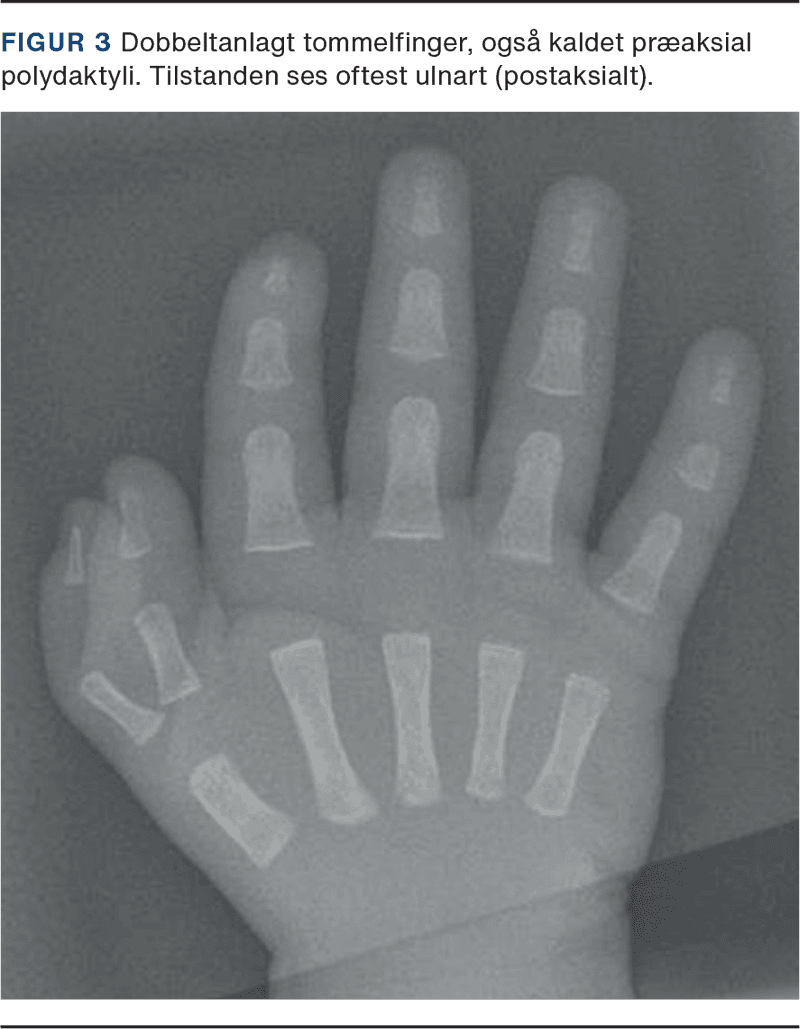

Børn med polydaktyli er født med ekstra fingre og/eller tæer. Tilstanden er relativt hyppig og skønnes internationalt at forekomme hos en ud af 1.500 nyfødte [1]. Ekstraanlægget kan variere i udvikling. Det ses hyppigst postaksialt (ulnart), men kan også sidde præaksialt (radialt) eller centralt. I Norden ses hyppigst ekstraanlæg på siden af femte stråle. Dette er oftest et stilket ekstraanlæg med en base på et par millimeter, hvor selve stilken udelukkende indeholder et kar og nervebundt.

I tilfælde af bilateral postaksial polydaktyli uden familiær historik henvises til genetisk udredning for bl.a. Bardet-Biedls syndrom. Bardet-Biedls syndrom er en sjælden genetisk sygdom, der hører ind under ciliopatierne. Syndromet kan medføre retinal dystrofi, adipositas, renal dysfunktion, indlæringsvanskeligheder, postaksial polydaktyli samt hypogonadisme [11] (Figur 3).